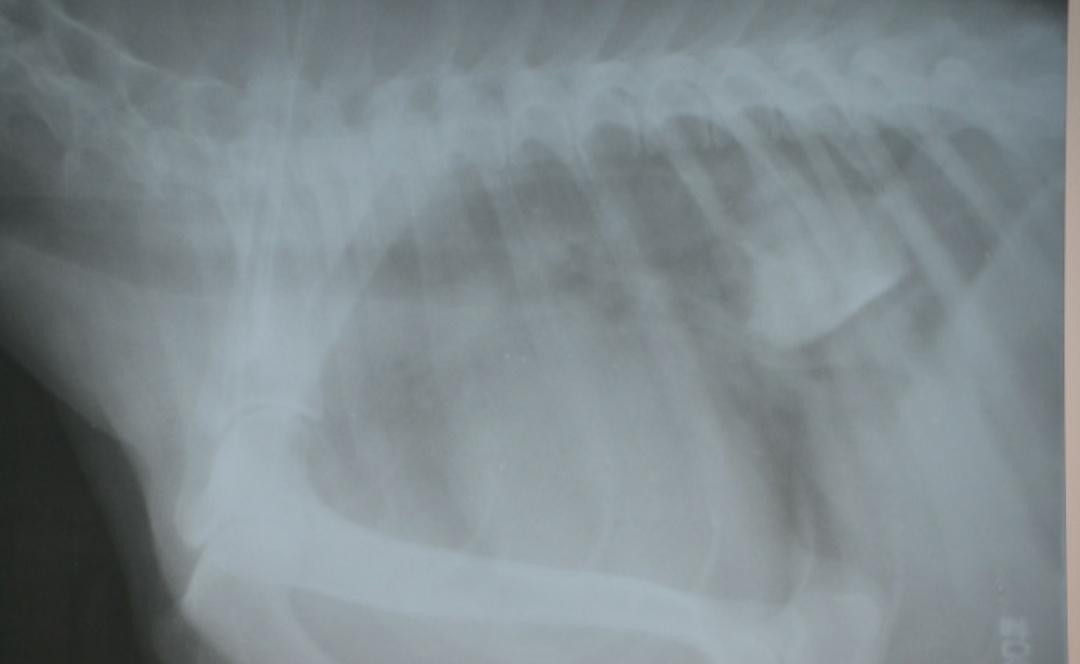

化验:X光片显示狗狗的食管末端,有一块骨头卡在上面,骨头还算比较规则。

治疗:灌服石蜡油和利多卡因,比较幸运的是这块骨头的位置特别靠近贲门,所以成功的用润滑剂,让骨头进入到了胃里面。

3天后再次拍X光,骨头完全消化,排出体内了。